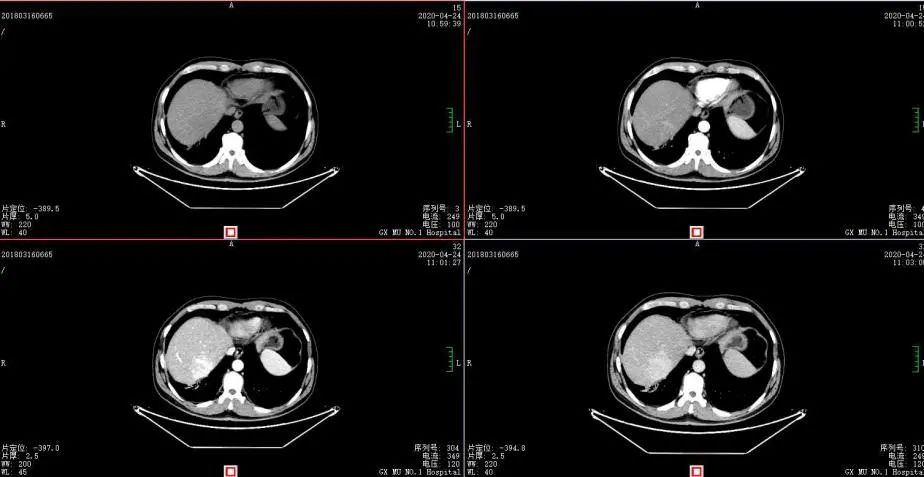

2020年4月复查:持续PR

肿瘤标志物:均正常

肝功能正常。

增强CT示:肝硬化

肝异常强化灶

考虑酒精性肝硬化可能性大,未基线使用替吉奥维持治疗。

胃癌并肝转移化疗后,肝内转移灶大致同期;

慢性肝病,脾大、门脉高压(食管下段-胃底静脉曲张);

纵隔淋巴结转移瘤,复查大致同前。